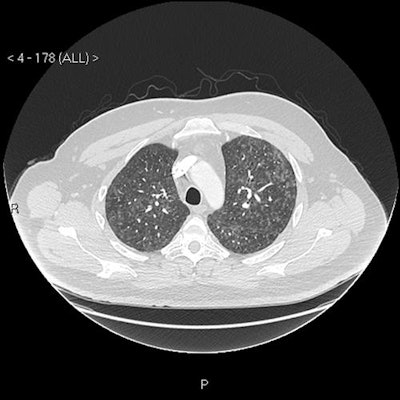

Imaging findings

"Our patient's CXR [chest x-ray] report was initially reported as normal (although we disagreed)," the authors wrote. "He subsequently had a CT pulmonary angiogram with high-resolution reconstruction (to exclude pulmonary thromboembolic as well as interstitial lung disease), reported as showing a ground glass, mosaic pattern in both lungs, with borderline enlarged hilar nodes, presumed reactive."